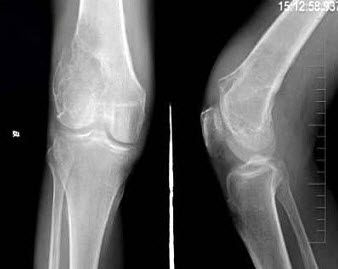

24、单项选择题

男,30岁,右膝关节酸胀,疼痛不适5个月,X线检查如图所示,最可能的诊断是()

A.骨巨细胞瘤

B.骨囊肿

C.骨血管瘤

D.动脉瘤样骨囊肿

E.以上均不正确